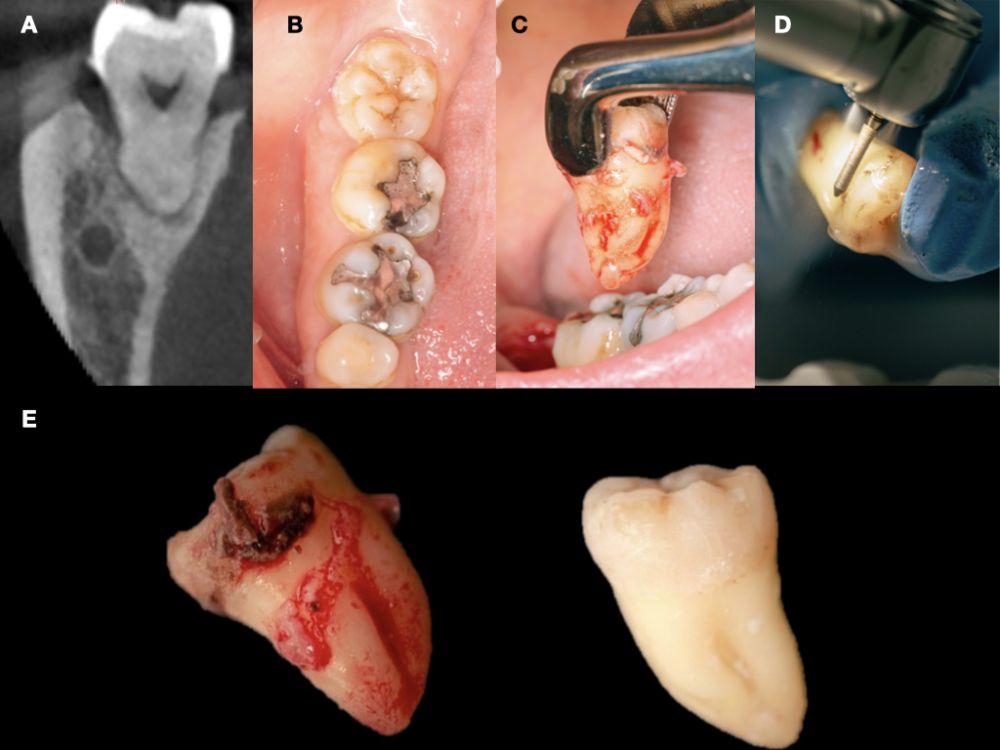

En la historia clínica, no se evidenciaron antecedentes médico-quirúrgicos de interés, alergias medicamentosas conocidas ni hábitos nocivos. A la exploración intraoral, se apreciaron las ausencias de 1.6 y 1.7 y la presencia del 1.8 y 4.8 (Figura 1). En la exploración radiográfica mediante escáner de haz cónico (CBCT) se apreció una altura residual de 5,0 mm en 1.6, donde se podría colocar un implante simultáneo, y de 2,6 mm en la zona del 1.7, dificultando la colocación de un implante de manera simultánea a la elevación de seno de acceso lateral (Figura 2).

Se planificó la exodoncia del 4.8 para utilizarlo como diente donante, para lo que se firmó previamente el consentimiento informado. Se realizó un bloqueo anestésico mediante articaína (Inibsa®, Barcelona, España) al 4% con adrenalina 1:100.000 del nervio dentario inferior, del nervio lingual y, por último, del nervio bucal. Al ser un diente sin procesos infecciosos asociados, únicamente se eliminó del diente el cálculo mediante instrumental ultrasónico y se realizó la extracción de la forma más atraumática posible. Se pulió la superficie radicular con fresas de diamante de turbina con abundante irrigación, eliminando de esta forma el ligamento periodontal (Figura 3).

Se registró el peso del diente una vez limpio en una balanza de precisión (Ohaus® YA 102, YA Gold Series, Nueva Jersey, EEUU) registrando 2,1 g de peso, y se cortó el diente en fragmentos ≤ 5 mm, colocándose secos dentro del molino del dispositivo Tooth Transformer® (S.R.L, Milan, Italia), tal y como indica el fabricante. Una vez introducido se colocó dentro del dispositivo y se añadió el recipiente con los líquidos, para desmineralizar el diente liberando BMP-2 y colágeno tipo 1, eliminando cualquier tipo de toxicidad residual. Cuando se insertaron todos los componentes la cubierta de la máquina se cerró y, presionando el botón de activación se inició el proceso hasta comprobar el molido de los fragmentos y el tamaño adecuado de partícula, gracias al tamiz que el recipiente recolector posee (400-800µm). En un plazo de 25 minutos se preparó el injerto de diente autólogo y se volvió a pesar en la balanza de precisión, registrando 2,6 g de peso (Figura 4).